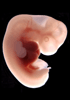

Carnegie Stage 17 (41 post-ovulatory days)

Most embryos at stage 17 are approximately 41 postovulatory days old and measure 11-14 mm in length. Distinguishing criteria for this stage include distinct digital rays in the hand plate, a rounded digital plate in the foot, a complete complement of hillocks on the mandibular and hyoid arches, distinct nasofrontal grooves, and a slight indication of a lumbar curvature.

This specimen does not represent normal development. The caudal nueral tube has failed to close properly.